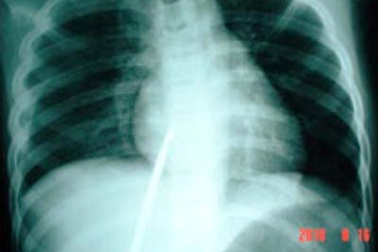

Sơ ý, một trẻ bị đâm thủng tim phổiTrong lúc đang săn chuột, T. bị một người bạn sơ ý đâm thẳng cây chĩa vào lồng ngực. Em được đưa tới bệnh viện trong tình trạng cây chĩa dài khoảng 2 mét ngập sâu vào cơ thể đâm thủng màng phổi phải và xuyên tâm thất phải.